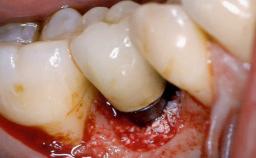

Surgical Management of Peri-Implantitis: Removal of Implant Due to Recurrent Infection Using an Implant-Retrieval Tool

Despite anti-infective surgical treatment, some patients may experience recurrent infection and progressive bone loss requiring additional treatment. This case describes a conservative approach using an implant retrieval tool without the need for excessive bone removal or use of a trephine.

A 65-year-old female patient was referred to the periodontist for assessment and management of infection associated with an implant at site 12. The general dentist had noted suppuration on probing during examination.